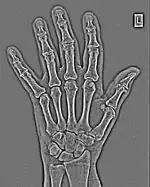

The essence of this approach is that it can be used to produce a range of image processing effects by enhancing and/or suppressing features in the 2D-FFT and then converting the result back into the spatial domain using the IFT, as illustrated in Figure 1.28. Such image manipulations are considered in more detail in a later chapter. Note that the form of image processing demonstrated in the figure is for purely illustrative purposes and bears no direct medical significance.

Fig. 1.28(c): The wrist radiograph processed by attenuating periodic structures of size between 5 and 20 pixels.